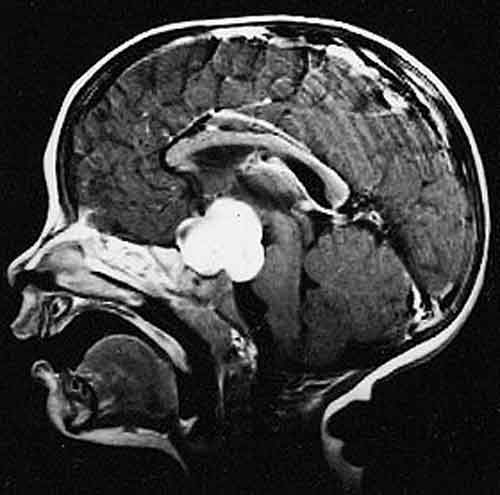

medulloblastoma

E’ la neoplasia cerebrale più frequente nei bambini. Uno studio fa luce sulle variazioni del Dna che lo causano

MILANO – Sono state identificate le mutazioni genetiche responsabili del medulloblastoma, il tumore maligno al cervello più frequente durante l’infanzia. Come spiegano i ricercatori americani della Stanford University e del Lucile Packard Children’s Hospital, nello studio pubblicato sulla rivistaNature , con questi risultati si potrà arrivare a cure meno tossiche e più efficaci nel giro di due anni. «Oggi si tende a trattare tutti i medulloblastomi come un’unica malattia – spiega Yoon-Jae Cho, coordinatore dello studio – senza considerare quanto siano diversi i tumori a livello molecolare. Con questa ricerca diamo una visione più accurata a livello genetico e apriamo la strada a nuove terapie».

MUTAZIONI GENETICHE – I trattamenti attuali per questo tipo di cancro, che ha origine dal cervelletto, comprendono l’intervento chirurgico e una combinazione di radio e chemioterapia, ma non sono «su misura» per le caratteristiche genetiche dei pazienti. I ricercatori Usa hanno estratto il Dna da 92 medulloblastomi mettendolo a confronto con i campioni di sangue degli stessi pazienti, scoprendo così 12 punti di mutazione significativi, cioè errori nel codice genetico che si verificano spesso in questo tipo di cancro cerebrale. Alcune di queste mutazioni erano già state identificate nel medulloblastoma, ma ora ne sono state individuate di nuove: «Adesso sappiamo che alcune forme di tumore hanno una particolare firma genetica – aggiunge Cho – che li rende resistenti alle terapie standard, per cui d’ora in poi potremo scegliere la cura più su misura per il profilo genetico del paziente. Potremo così ottenere risultati migliori e ridurre gli effetti collaterali». (Fonte Ansa)